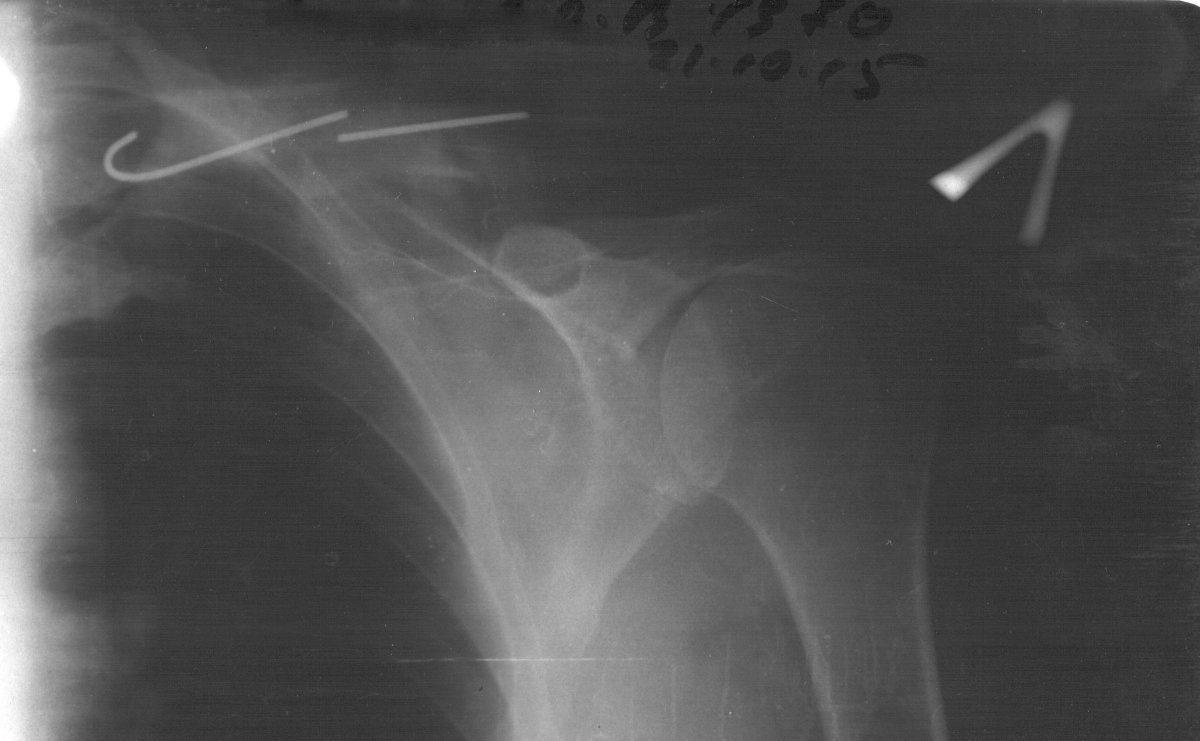

Скан, камрады прошу не обсуждать чудо средства итд, мне это не нужно

Images:

klch2.jpg

Спица лопнула от перенагрузки. Ключица нормально не сопоставлена. Дальше два пути на выбор топика. Первый и самый жизненный - оставить всё как есть, но в этом случае нельзя давать те нагрузки которые привели к перелому спицы. Второе - раскрыть - сломать, нахрен, ключицу, выдернуть обломок старой спицы, провести новую. В последнем случае, затратном материально, 2-2,5 мес. нетрудоспособность, а полную нагрузку можно давать не ранее 6 мес. от операции.

9 из 10 человек не идёт на второй вариант. Обычно это не сказывается на работоспособности в пределах нормальных нагрузок.

Говорил сегодня с травматологом и хирургом (они друг друга не знают) травматолог сказал (я пишу итог) достать часть могу, не будет тревожить пусть остаётся, хирург сказал без проблемм 3года может быть спица а там как повезёт , рекомендует все же её убрать

Еслиб это было у меня, если нет снижения\утраты функции, нет болевых ощущений и тп, оставил бы как есть. через пол года, год и полтора сделал бы контрольные снимки, чтоб убедиться что вокруг спицы нет признаков\очагов деструкции костной ткани или других признаков патологических изменений костной ткани. А дальше по ситуации... При появлении болевых ощущений, дискомфорта и тп - операция по удалению спицы.